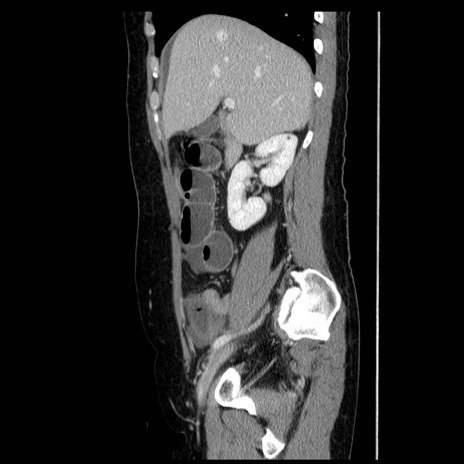

冠状断像